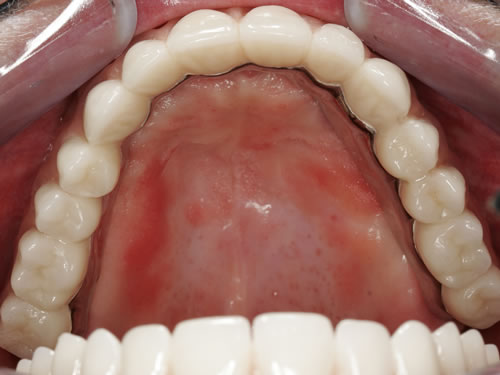

Für den zahnlosen Ober- und Unterkiefer werden dies häufiger Stegkonstruktionen oder Teleskopversorgungen sein (Abb. 8.8 bis 8.16).

Abb. 8.10: Individueller Stahlsteg auf 4 Implantaten im zahnlosen Oberkiefer.

Abb. 8.11: Eingegliederter graziler, herausnehmbarer, gaumenfreien Zahnersatz.

Abb. 8.12: Zahnloser Oberkiefer mit 8 Implantaten und eingesetzter Unterkonstruktionen.

Abb. 8.13: Abnehmbare, grazile Brücke.

Abb. 8.14: Zahnloser Oberkiefer mit vier Teleskopen.

Abb. 8.15: Ansicht des Zahnersatzes von unten.

Abb. 8.16: Eingegliederter gaumenfreier Zahnersatz.

Auch eine festsitzende zementierte oder verschraubte Brücke ist möglich (Abb. 8.17 bis 8.19). Hierbei muss eine günstige Lachlinie vorliegen und der Kieferschwund sollte noch nicht zu weit fortgeschritten sein. Die Zähne würden sonst sehr lang wirken, da die Zahnpositionen in die ehemalige Position der Zähne zurückgebracht werden muss. Langes Prothesentragen und entsprechender Knochenverlust erschweren besonders im Oberkiefer festsitzenden Zahnersatz. Sehr exakte Voruntersuchungen und präzise Implantatpositionen mit entsprechenden Knochenaufbaumaßnahmen sind häufig notwendig, um den Patienten diesen Wunsch zu erfüllen.